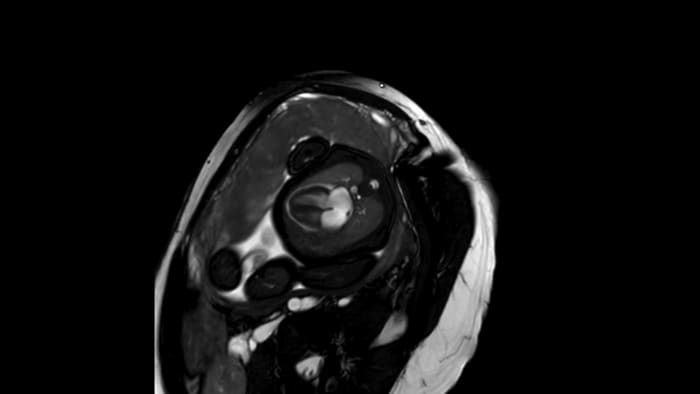

Fetal cardiac imaging examples, gestational age 33-36 weeks.

Short axis view, 1.5T

Short axis view, 3.0T